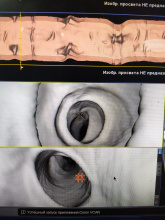

Как и обещал фото в студию. Извеняюсь что на телефон, но вытянуть диком через Радиант нельзя, так как там нет режима вирт.колоноскопии.

3D  визуализация для оценки модели все толстой кишки. Как видно прога автоматически опредялеят ход кишки и ее удлинение с доп.изгибами.

Перорально принятый контраст делает стенки раздутой кишки более четкими

также контраст пропитывает оставшиеся фрагменты фекалий, делая их дифференцируемыми, особенно таких которые могут напоминать полип.

ну и собственно внутренняя картина